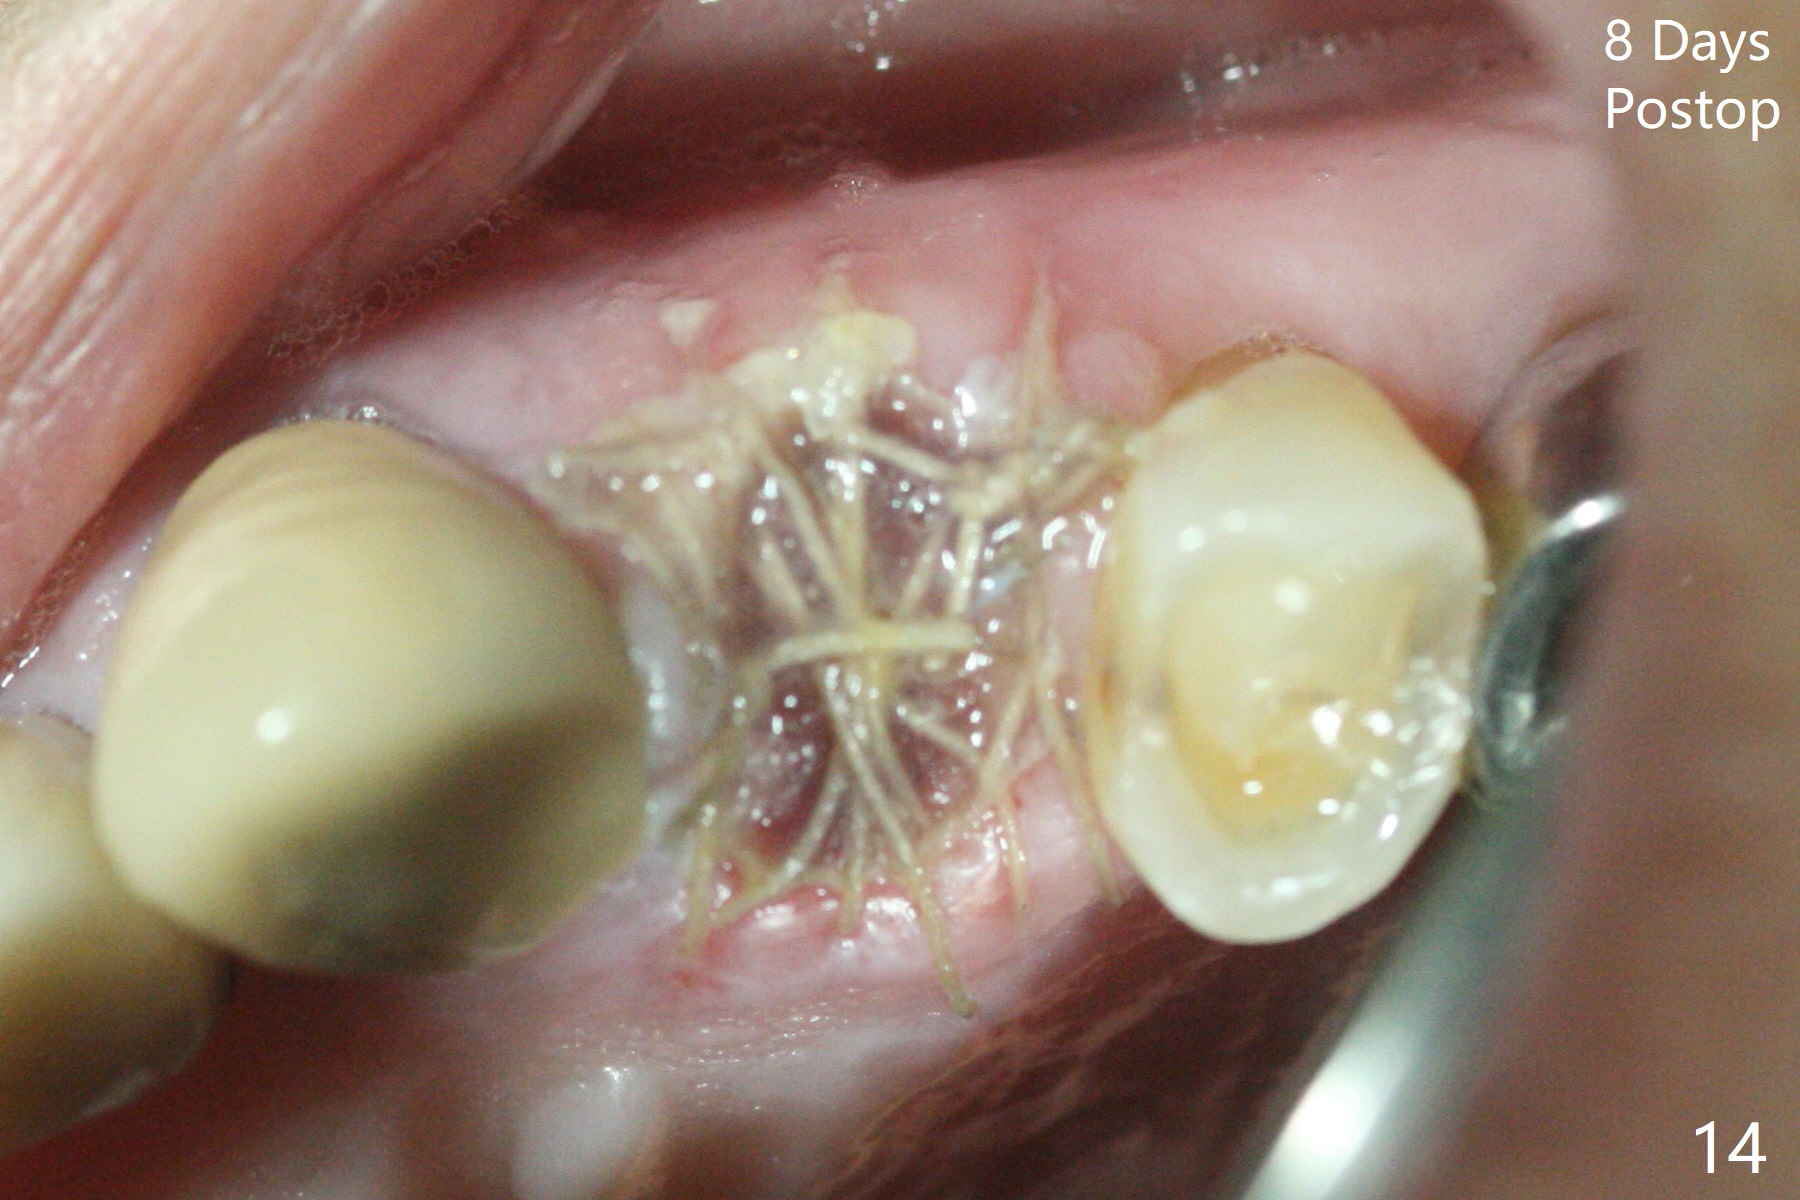

68岁女左上4颊侧瘘道(图一:*),与根尖颊侧骨板缺失相通,其实腭侧根尖周围病变更大(也与颊侧窝相通),术中没有注意腭侧根接近3(图二:P),稀里糊涂的基本顺着腭侧根(颊侧)走向钻洞(图四,与图三理想方向对比),突然记起术前设计钻洞必须在腭侧牙槽窝远中颊侧,在远中建立新洞眼(图五),之后无法再次建立新洞眼,只好利用同一个侧面切割钻头将钻洞往远中移位,同样效果不佳(图六),最后只好放弃,放置粘性骨粉(图七:*),覆盖PRF膜,6个月胶原膜,PGA缝线,牙周胶水。术后重新分析表明顺着腭侧牙槽窝种植与尖牙还是有分离(图八,九:*),因为牙槽窝是斜型的(图十:黑色),不过离颊侧骨板也接近(图八:B)。所以钻洞必须斜型针对远中骨壁,表浅些(图十一:红色箭头);一旦进入骨板,改变角度(图十二:红色箭头),适当矫枉过正,随着植体增大,钻洞会往近中偏移(白色箭头)。最好植体方向理想(图十三)。不过植骨后钻洞偏移可能性比较少。缝线和牙周胶水似乎是一个稳妥固定胶原膜方法。术后病人抱怨水肿严重,术后八天颊侧根尖隆起是由于骨粉推出骨板之外(图十五,十六:*),上颌窦底板无意穿孔(^)伴有上颌窦膜(M)增厚,与术前对比(图十七:上颌窦窦腔清晰)。术后一个月6个月吸收膜不见了,大多数缝线已经脱落,最后两根缝线撤除后,牙槽窝开口已经关闭,好像主要成分是骨粉(图十八)。术后5个月牙槽嵴宽,角化龈也宽,好像可以植入4x11.5毫米植体(图十九)。